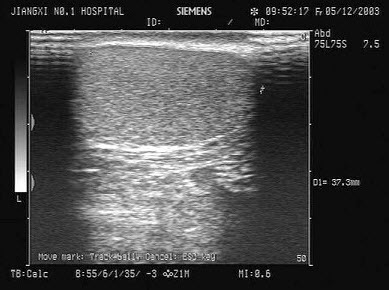

16、单项选择题

如图,正常甲状腺中部横切面的超声声像图,中央气管环状软骨前方组织为()

A.甲状腺峡部

B.皮下组织

C.甲状旁腺

D.淋巴结

E.以上均不对